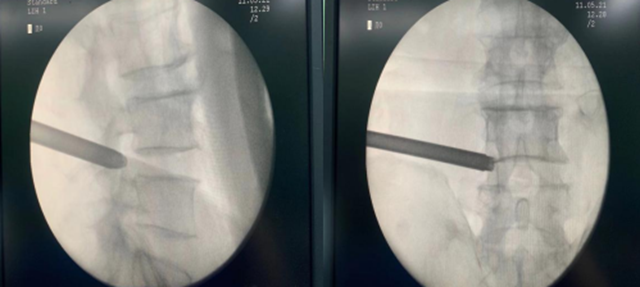

次日在刘庆教授团队的共同努力下,手术顺利完成。术中,韩聪医生从她腰椎取出10颗破碎的髓核。术后,刘嬢嬢很快觉得腰部、腿部一点也不疼了,第二天就能下床,前后不到一周就出院了。

椎间孔镜与脊柱内窥镜类似,是一个配备有灯光的管子,它从病人身体侧方或者侧后方进入椎间孔,在安全工作三角区实施手术。在椎间盘纤维环之外做手术,在内窥镜直视下可以清楚地看到突出的髓核、神经根、硬膜囊和增生的骨组织,然后使用各类抓钳摘除突出组织、镜下去除骨质、射频电极修复破损纤维环。